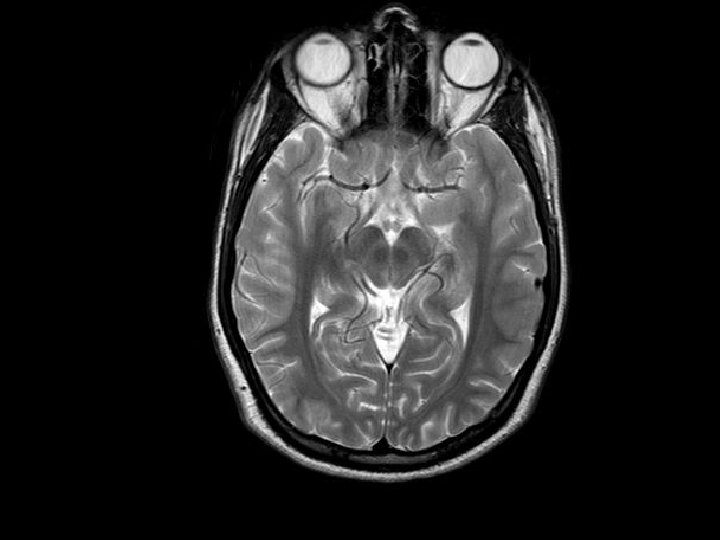

Brainstem Activation in Migraine Headache Weiller et al. Bahra et al. Afridi et al. Nat. Med. 1995 Lancet 2001 Brain 2005

Craniovascular Activation in Primary Headaches Cluster Headache MRA Migraine